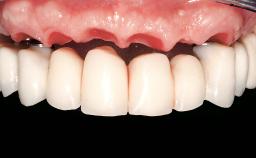

Immediate Loading of Six Implants in the Mandible and Six Implants in the Maxilla and Final Restoration with Full-Arch CAD/CAM Metal Framework FDPs Involving Digital Planning and Guided Surgery

Prosthesis Type FDP

Loading Protocol Immediate

Retention Screw-retained, with 4 or more splinted implants Screw-retained, with 4 or more splinted implants